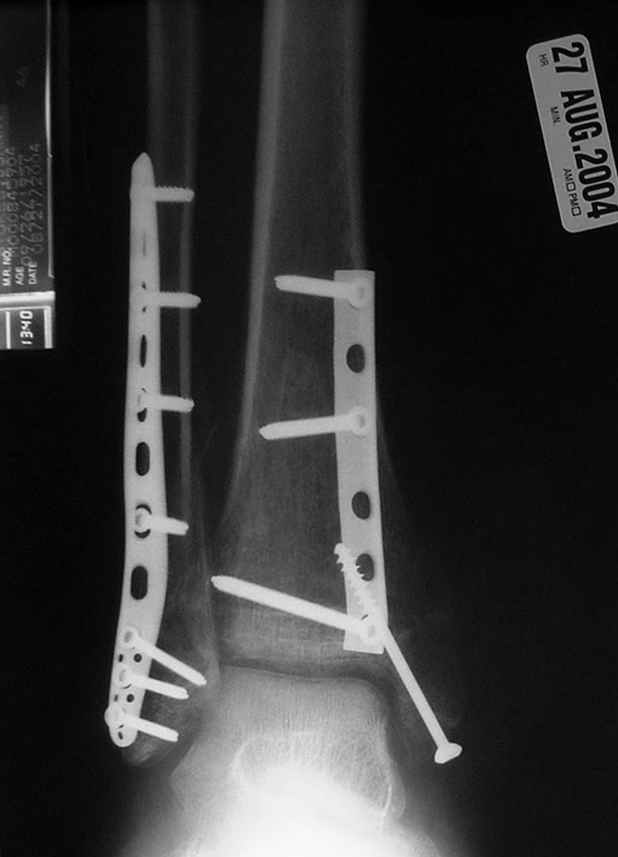

Второй случай сделан из одного разреза

На прямой проекции послеоперационного Рг макроскопически все выглядит очень анатомично, при микроскопическом ( :-)) ) рассмотрении можно все-таки заметить вальгизацию тарана, суставная щель в латеральном отделе сустава несколько уже , чем в медиальном при отсутствии латерального смещения тарана. У меня был аналогичный случай (без LISS , без мини доступа) с вальгусным наклоном тарана при восстановленном ankle mortise при последовательном наблюдении с интервалами в 6-8 недель в послеоперационном периоде отмечалось прогрессирующее сужение суставной щели в латеральном отделе сустава, закончившееся посттравматическим ОА, к счастью боли умеренные, купируемые аналгетиками или своими эндорфинами:-))(активная пациентка, у которой нет времени на болезни....) Какова жизненная ситуация в приведенном вами случае? И последнее, что я хотел бы прояснить для себя - фиксация внутренней лодыжки: я обычно комбинирую фиксацию компрессирующим винтом со спицей - по идее ротационная стабильность должна быть лучше, чем один винт, каковы ваши наблюдения в этом плане?